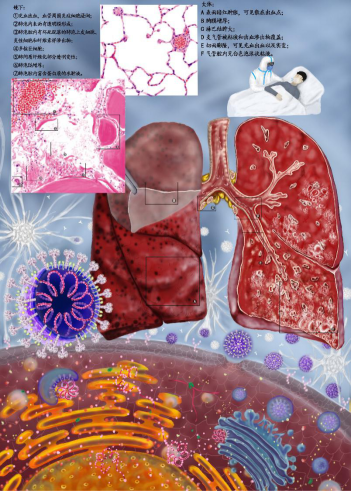

二等奖作品(2):动脉粥样硬化 作者:17临床医学 陈沁